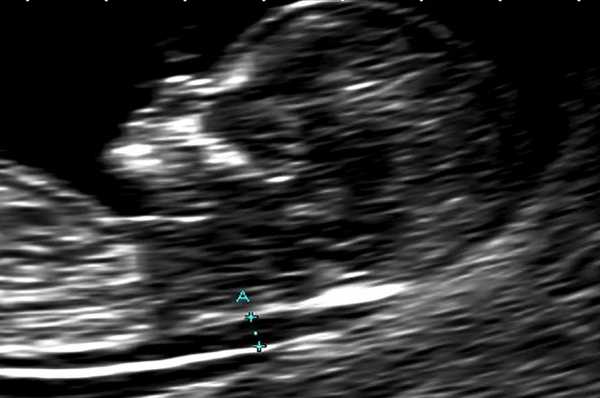

В основной группе численные значения расширенного воротникового пространства плода варьировали от 2,5 до 11,0 мм и превышали соответствующие показатели (5-й, 50-й, 95-й центиль) в группе сравнения в 11–12, 12-13 и 13-14 недель беременности (рис. 1).

Рис. 1. Увеличение толщины воротникового пространства